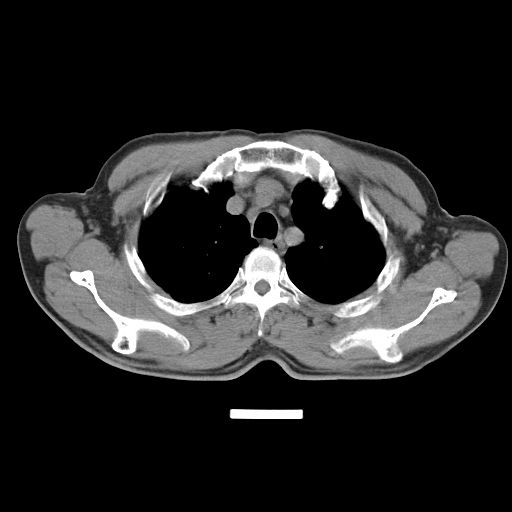

以下是引用心路寻觅在2010-3-1 10:23:00的发言:[br]1、考虑左肺上叶周围型肺癌[br]2、右上肺陈旧性病灶。[br][br][本贴已被 心路寻觅 于 2010-3-1 10:40:18 修改过]

以下是引用shuiyuan在2010-3-1 10:45:00的发言:[br]考虑左肺上叶中心型肺癌伴阻塞型炎症,邻近胸膜受侵。